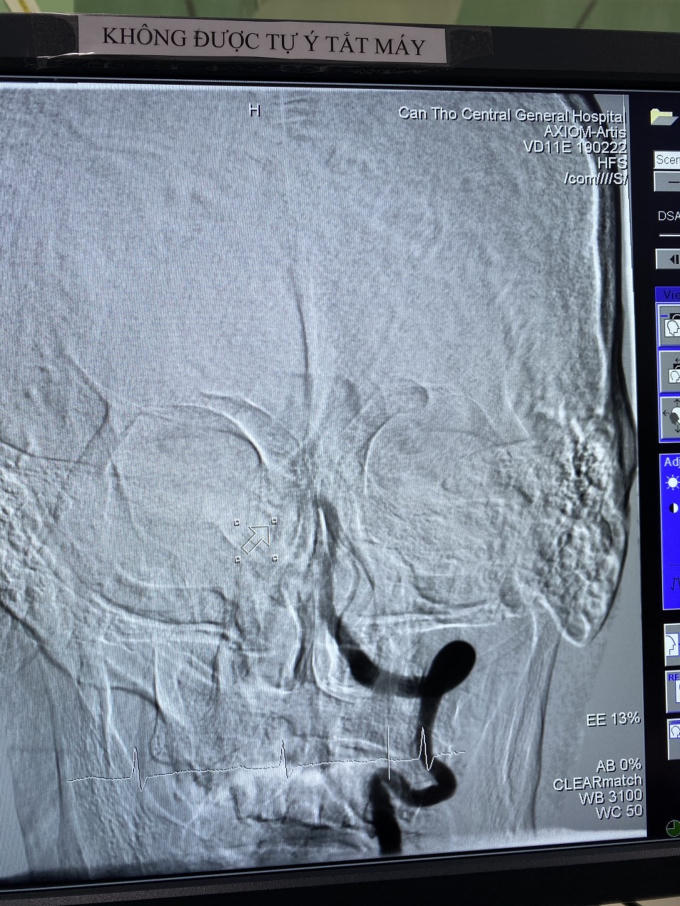

Thăm khám, kết quả chụp CTscan não bệnh nhân bị tắc động mạch thân nền từ vị trí hợp lưu đến đỉnh thân nền. Bệnh nhân bị tắc mạch ở vị trí này nguy cơ tử vong rất cao nếu không can thiệp tái thông mạch máu và nếu can thiệp muộn thì di chứng rất nặng nề, bệnh có thể sống đời sống thực vật hoặc liệt tứ chi.

Hình ảnh động mạch thân nền trước tái thông.